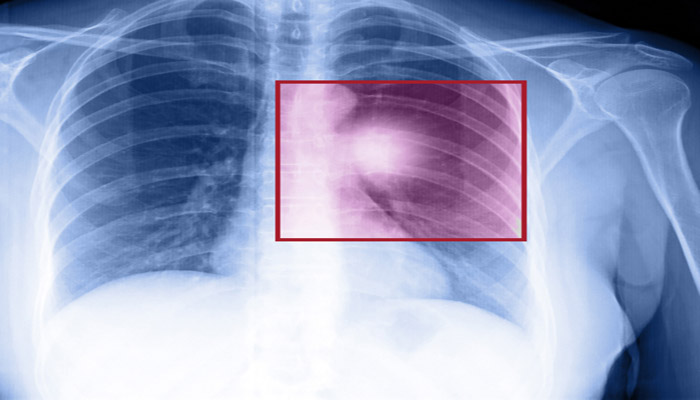

Akciğer kanserinde yeni hedefli tedavilerle yaşam süresinde önemli artış bekleniyor!

Akciğer kanseri yeni nesil tedavilerle yaşam süresi ve kalitesi önemli ölçüde artıyor!

Kanser Haftası’nda akciğer kanseri tedavisinde gelecekte bizi nelerin beklediğini anlatan Türk Akciğer Kanseri Derneği (TAKD) Danışma Kurulu Üyesi Prof. Dr. Nil Molinas Mandel, “Çok yakın bir gelecekte eskiden metastazlı akciğer kanseri için 3-6 ay dediğimiz yaşam sürelerinde ciddi bir artış göreceğiz. Biz 1 yıllık yaşam süresine baktığımız zaman eskiden yüzde 15-20 olan oran, bugün %60'lara çıktı” dedi.

Prof. Dr. Nil Molinas Mandel, akciğer kanserinin günümüz tedavi yaklaşımındaki değişimleri şu sözlerle açıkladı: “Öncelikle, akciğer kanserini kabaca küçük hücreli ve küçük hücreli dışı kanser olarak iki alt gruba ayırıyoruz. Küçük hücreli dışı akciğer kanserlerinin alt gruplarını belirlemek ve uygun hastalarda, tümörün genomik yapısını, mutasyon varlığını araştırarak tedavi planlamak standart yaklaşım oldu. Çok yakın bir gelecekte, bazı moleküllerin hem yan etkilerini hem etki mekanizmalarını tanıdıkça, sayıları giderek artacak uzun bir ilaç listesi oluşacak. Bu ilaçlarla, eskiden metastazlı, ileri evre akciğer kanseri için 3-6 ay dediğimiz yaşam sürelerinde ciddi bir artış göreceğiz. Biz 1 yıllık yaşam süresine baktığımız zaman eskiden yüzde 15-20 olan oran, bugün %60'lara çıktı. Yani, hastaların yarısından fazlası metastazlarına rağmen, 1 yılın üzerinde yaşayabilir hale geldi. Dolayısıyla akciğer kanseri tedaviden istifade edebilen bir kanser türüdür diyebiliriz.”